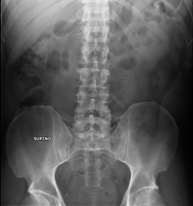

- RX Abdomen

Tècnica que usa els raigs X a través de la qual s'obtenen imatges de l'abdomen (estómac, intestí prim, intestí gros, fetge, ronyons, bufeta, pelvis òssia, etc.) per al seu estudi. - RX Columna lumbar

- Pelvis X-ray

This procedure uses X-ray imaging to examine the pelvis, especially the pelvic bones.